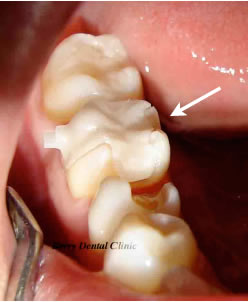

下の画像のように小さい銀歯の人工物からセラミック系の修復物も取り扱っております。

上の画像のセラミックインレーを試適しています。

色や厚み等検査してから問題ないようでしたら次回セラミックインレーをセットします。